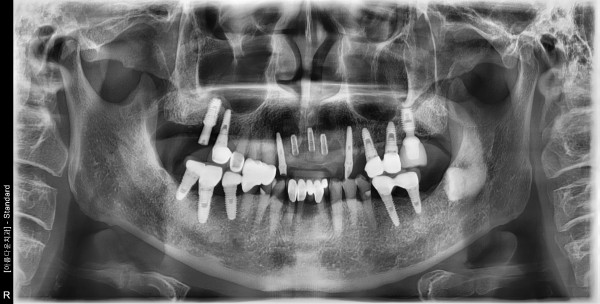

70대 남성 임플란트 식립